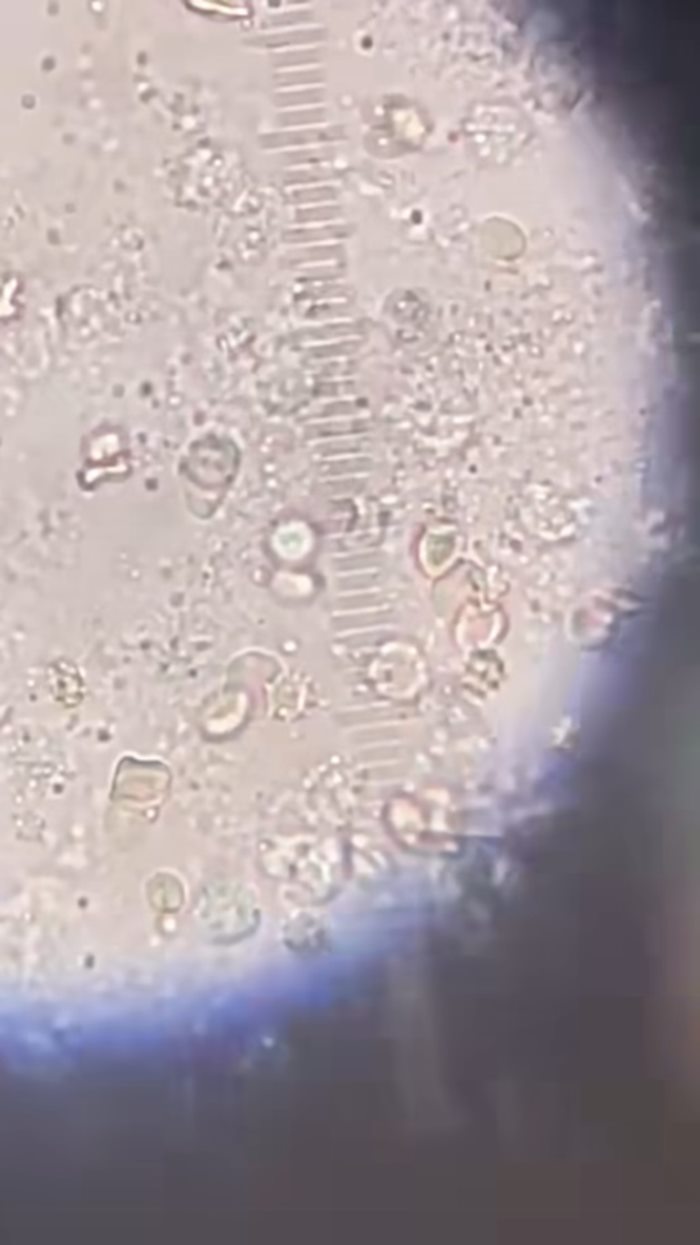

ถามประวัติคนไข้ว่ามีการกินของดิบไหม คนไข้เผยว่า ตอนปกติไม่กิน แต่ตอนเมาไม่รู้ ทำให้แพทย์สงสัยว่าอาการที่เกิดขึ้นอาจจะเป็นเพราะกลุ่มพยาธิ จึงทำการส่องกล้องหลอดลม ก็เจอแจ็กพ็อตว้าวุ่นเลย มีพยาธิใบไม้ปอดวิ่งไปวิ่งมาเต็มไปหมด

โดยพยาธิชนิดนี้

เป็นพยาธิชนิดหนึ่งที่อาศัยในปูน้ำจืด คนชอบเอาไปใส่ตำปูปลาร้า

เพราะคิดว่าดองเค็มแล้วพยาธิจะตาย แต่ความจริงมันไม่ตาย เมื่อคนกินเข้าไป

พยาธิก็จะไชออกมาจากลำไส้ จากนั้นก็ขึ้นไปตับ ขึ้นไปในปอด

เกิดโพรงฝีในปอดนั่นเอง